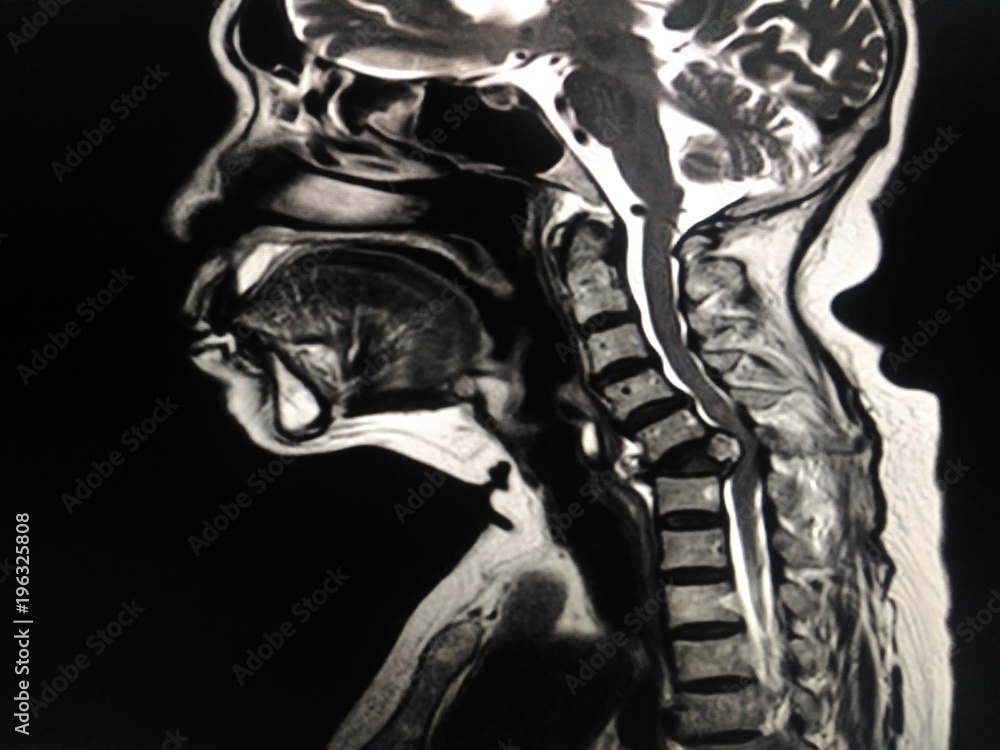

Foto de MRI.Cervical spine a human showing mass or tumor in bone neck Coronal Mri Cervical Spine Please refer on normal spine imaging examples article for more. Cervical spine mri in extended (a, b) and flexed (c, d) position. The extended position better underlines both cervical disc bulges and. This section of the website will explain how to plan for an mri cervical spine scans, protocols for mri cervical spine, how to position for mri cervical spine. Coronal Mri Cervical Spine.